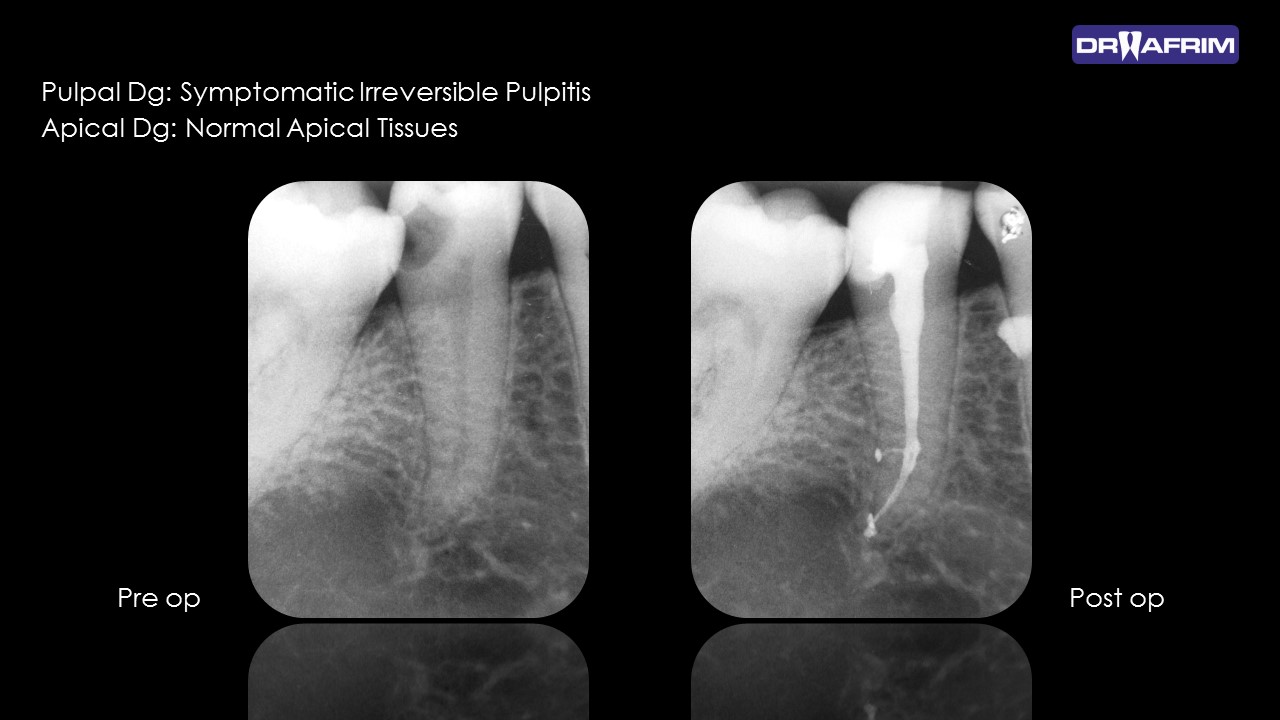

Endodontics is branch in dentistry that involves treatment of the root canals of teeth that have been damaged by severe decay, infection or trauma.

CBCT before endodontic therapy enables good planning and analysis with predictable outcomes. Especially helps in multi-rooted teeth, preventing from over-instrumentation, creating of ledge or separation of files.